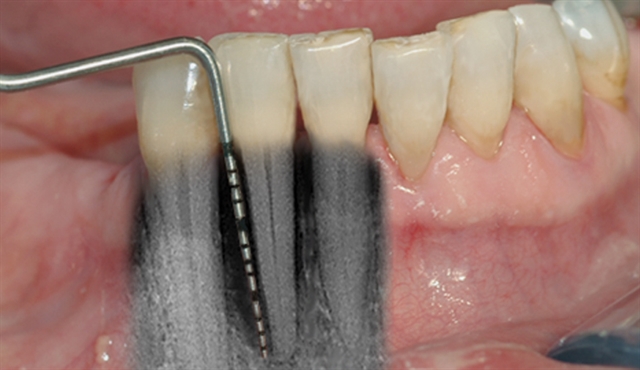

• Ei undersøking med lommeregistrering avdekkjer likevel eit omfattande beintap ved den eine

tanna.

• Instrumentet er her lagt utanpå tannkjøtet for å vise kor omfattande festetapet er.